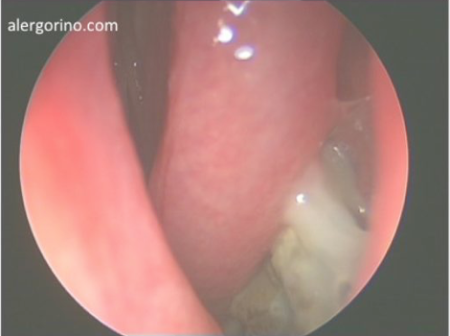

endoscopia nasalendoscopia nasal

El diagnóstico se realiza mediante la historia clínica y una endoscopia nasal que proporcionan datos como la presencia de pólipos, la descarga mucopurulenta y el edema o la obstrucción de las áreas de drenaje de los senos paranasales. Si no se produjera una respuesta al tratamiento médico se evalua la situación de los senos paranasales mediante una tomografía computarizada (TC).